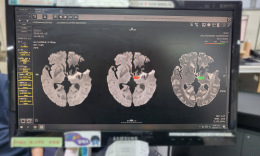

공지사항 언론보도 활동사진첩 오늘의 식단 1:1 문의게시판 병원소식 - 공지사항 - 언론보도 - 활동사진첩 - 오늘의 식단 - 1:1 문의게시판 Home 병원소식 언론보도 지역 종합병원들, “의사 없으니 AI라도 쓰게해달라” by 관리자 Mar 20, 2026 1 Readed 지역 종합병원들, “의사 없으니 AI라도 쓰게해달라” 보건복지부 각종 지원 사업 인력 기준 '현실성 제로' 지적 “의사 대신... 부산 온병원, “췌장·담도 질환, 대기없이 당일 검사” by 관리자 Mar 18, 2026 3 Readed 부산 온병원, “췌장·담도 질환, 대기없이 당일 검사” 췌장담도센터 박은택 센터장·소화기내과 황종호 과장 팀 구축 대학병... 온그룹재단 직장금고, 출범 2년 만에 ‘배당 10%’ 대박 by 관리자 Mar 16, 2026 4 Readed 온그룹재단 직장금고, 출범 2년 만에 ‘배당 10%’ 대박 직원 대출 금리 3.49% 등 ‘파격 복지’ 실현 재단 지정 금고…자... 119-2차-대학병원, 사선에서 빛난 ‘환상의 트라이앵글’ by 관리자 Mar 12, 2026 10 Readed 119-2차-대학병원, 사선에서 빛난 ‘환상의 트라이앵글’ 부산 온병원-부산대병원, 중증 외상환자 구호 협력 모델 완성 저혈압·저체... “심정지 소생률 40%”…온병원, 전국 평균 4배 웃돌아 by 관리자 Mar 09, 2026 13 Readed “심정지 소생률 40%”…온병원, 전국 평균 4배 웃돌아 2025년 심정지 환자 130명 내원, 52명 귀중한 생명 되살려 응급실 소생률 40% ... “어느 과로 가야죠?” 진료벽 허문 ‘통합내과’ 주목 by 관리자 Mar 05, 2026 40 Readed “어느 과로 가야죠?” 진료벽 허문 ‘통합내과’ 주목 부산 온병원, 내과 전문의 3인 배치…복합질환자 ‘진료 핑퐁&... 온병원, 개원 16주년 맞아 베트남-러시아 진출 선언 by 관리자 Mar 03, 2026 13 Readed 온병원, 개원 16주년 맞아 베트남-러시아 진출 선언 베트남·극동러시아 분원 설립-20층 규모 서면 ‘엘리온 여성메디타운’ 추진 &l... 삼일절, 한-러 두 의사가 피운 8년 우정의 꽃 by 관리자 Mar 02, 2026 14 Readed 삼일절, 한-러 두 의사가 피운 8년 우정의 꽃 러시아 하산중앙병원장 예브게니, 방한 중 그린닥터스 봉사 동참 정근 이사장과 2018년 첫 인연…... 부산 온병원, PET-CT 검사 3,000건 돌파 by 관리자 Feb 27, 2026 11 Readed 부산 온병원, PET-CT 검사 3,000건 돌파 2018년 도입 후 7년여 만의 쾌거…‘지역 암·뇌질환 파수꾼’ 우뚝 암 검사가 84%로 &... “심층진찰보다는 집단지성인 다학제 진료 확대를” by 관리자 Feb 26, 2026 18 Readed “심층진찰보다는 집단지성인 다학제 진료 확대를” 대한종합병원협회, "의사 1인 15분보다, 5인 15분이 중증환자에 도움“ AI 기반 신... 국제종교연합, 인도 아삼에 ‘K-지혜’ 심는다 by 관리자 Feb 23, 2026 8 Readed 국제종교연합, 인도 아삼에 ‘K-지혜’ 심는다 범어사 선문화교육관서 3월 말까지 ‘인도 아삼 봉사 사진전’ 개최 현지 ‘... ‘극저온 냉각치료’로 흉부 수술 후 ‘마의 통증’ 잡는다 by 관리자 Feb 23, 2026 10 Readed ‘극저온 냉각치료’로 흉부 수술 후 ‘마의 통증’ 잡는다 부산 온병원, 최첨단 ‘CRYO 냉각통증치료’ 부울경 최초 ... 겨울철 안경 김 서림, 낙상 사고 주의보 by 관리자 Feb 19, 2026 11 Readed 겨울철 안경 김 서림, 낙상 사고 주의보 치악산 하산 중 선글라스 성에로 10m 추락사고 발생 시야 흐려진 채 보행시 사고 2.5배 급증, 고령층 치명적 ... 부산 소방-의료계 맞손, ‘응급실 뺑뺑이’ 비극 끊어낸다 by 관리자 Feb 13, 2026 15 Readed 부산 소방-의료계 맞손, ‘응급실 뺑뺑이’ 비극 끊어낸다 재이송 시 119 재투입 파격 협약…“수용 거부 명분 없앤다” 앞... 그린닥터스, 북한 의약품 보내기 운동 전개 by 관리자 Feb 12, 2026 18 Readed 그린닥터스, 북한 의약품 보내기 운동 전개 3월 말까지 집중 모금…정부 및 제3국 루트 등 다각도 검토 개성공단서 8년간 35만 명 진료…&... 정근안과병원, 96세 초고령·난청 백내장 수술 성공 by 관리자 Feb 10, 2026 18 Readed 정근안과병원, 96세 초고령·난청 백내장 수술 성공 8년 전 전신마취 권유로 대학병원 수술 포기, 10분 만에 ‘광명’ 심한 난청&midd... ‘디지털 PET-CT’로 암부터 치매·파킨슨까지 by 관리자 Feb 09, 2026 21 Readed ‘디지털 PET-CT’로 암부터 치매·파킨슨까지 온병원, 2025년 510건 시행 ‘암 넘어 뇌 질환 정밀 진단까지’ 초기 알츠하... 온닥터TV, ‘대한민국, 종교에서 길을 묻다’ 8일부터 잇단 방송 by 관리자 Feb 03, 2026 15 Readed 온닥터TV, ‘대한민국, 종교에서 길을 묻다’ 8일부터 잇단 방송 정여 스님·임영문 목사·신요안 신부 등 종교계 거목 3인 릴... 개원 16년 온병원, 부산 대학병원들과 어깨… 20대 만족도 ‘1위’ by 관리자 Feb 03, 2026 20 Readed 개원 16년 온병원, 부산 대학병원들과 어깨… 20대 만족도 ‘1위’ 바로미터여론연구소, 부산 700병상 이상 대형병원 만족도 조사 발... “남편이 잃어버린 기억, 누군가의 발이 되길…” by 관리자 Jan 30, 2026 21 Readed “남편이 잃어버린 기억, 누군가의 발이 되길…” 10년 치매 병수발 하다 남편 사별한 80대 아내의 사부곡(思夫曲) 부산 온요양병원에... 목록 제목+내용제목내용댓글이름닉네임아이디태그 1 2 3 4 5 6 7 8 9